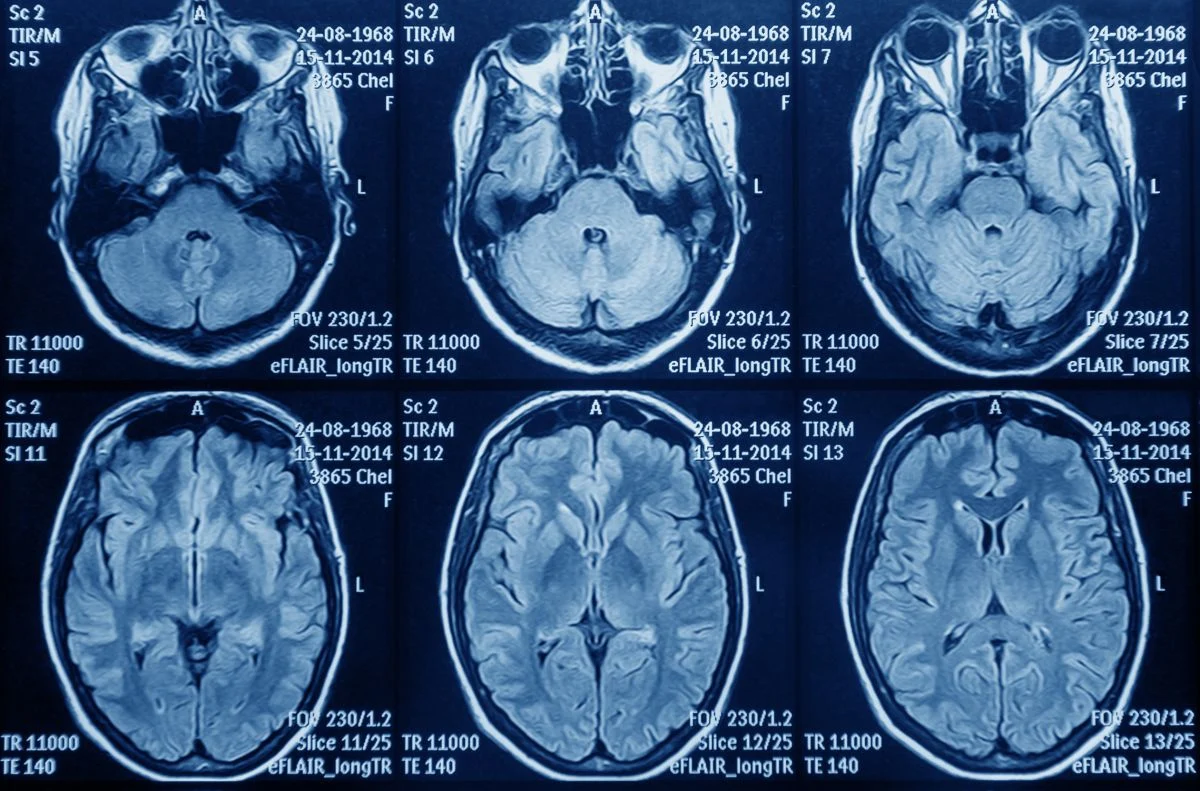

Según explicó Astuce, el glioblastoma es el tumor cerebral más agresivo y con peor pronóstico, con una mediana de supervivencia de apenas 14,6 meses con el tratamiento estándar, que combina cirugía, radioterapia y quimioterapia con temozolomida. A pesar de este pronóstico, el estándar de tratamiento ha permanecido estático en España durante más de dos décadas.

Sin embargo, en los últimos años, estudios clínicos han demostrado que el uso de TTFields, un dispositivo que emite campos eléctricos para frenar la proliferación de las células cancerosas, puede aumentar significativamente la supervivencia cuando se combina con la quimioterapia de mantenimiento. De hecho, las guías internacionales (NCCN) y nacionales, incluyendo las de la Sociedad Española de Oncología Médica (SEOM) y el Grupo Español de Investigación en Neurooncología (Geino), recomiendan la incorporación de los TTFields como parte del estándar de tratamiento del glioblastoma de nuevo diagnóstico.